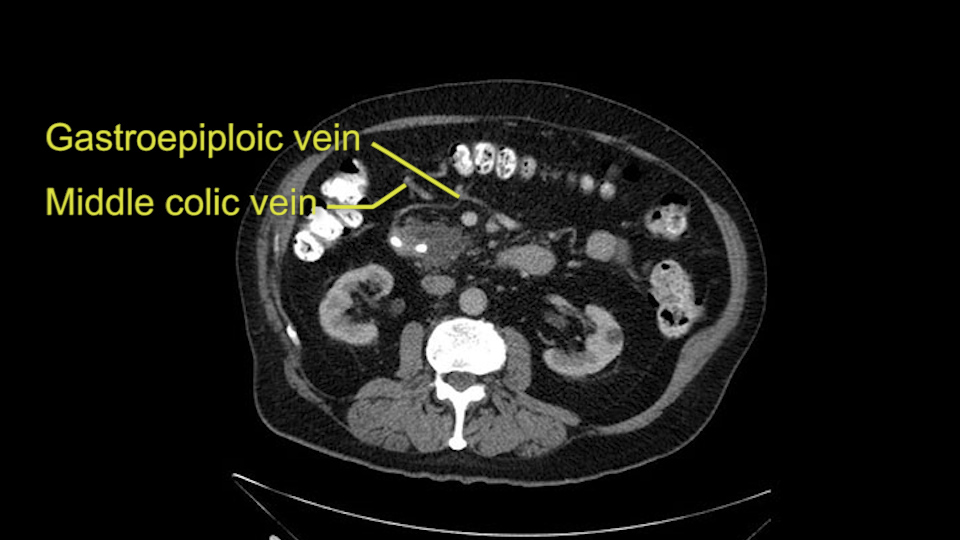

The other thing I look at is the gastroepeiploic arcade- which is this thing here- which is where the gastroepeiploic vein joins the portal vein. I call it the gateway to the neck of the pancreas because you pretty much have to divide it to get to the neck. The middle colic vein usually drains either into it or nearby. I think we’re seeing it here. Again,that can be divided and I usually divide those two and it helps me get under the neck. Again, there’s no issues here with the tumor so it’s nice from that perspective. If I was concerned about the vein, which I’m not here, I would go to the coronal view. It’s a nice way to look at the vein on just a couple of cuts and you can see a beautiful view of it here. There’s the portal vein, there’s the head of the pancreas. There’s the tumor. It’s a little closer here than it looks on the other one. I doubt it’s involved. If it’s touching, it may not be invading it but even if it was, it's a short segment. Anyways, there’s the SMV there’s the splenic vein, and everything looks good. You can see the stent. I ignore the stent. It’s the most dramatic looking thing in the picture but it’s actually the least important.